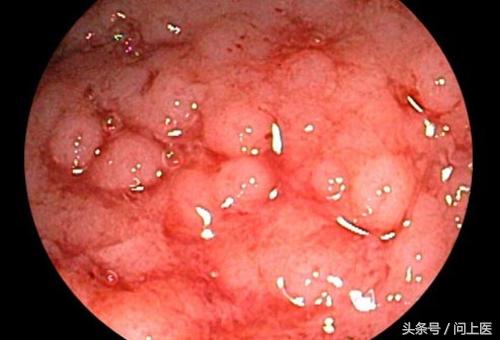

8 / 24 溃疡性结肠炎的诊断

溃疡性结肠炎最准确的检查方法是结肠镜检查,在该检查中,医生会将一个小型相机插入患者的直肠内,以近距离地视察结肠内部,可以视察到该部位是否有溃疡或炎症。医生也会通过该检查来排除克罗恩病、憩室炎和癌症。